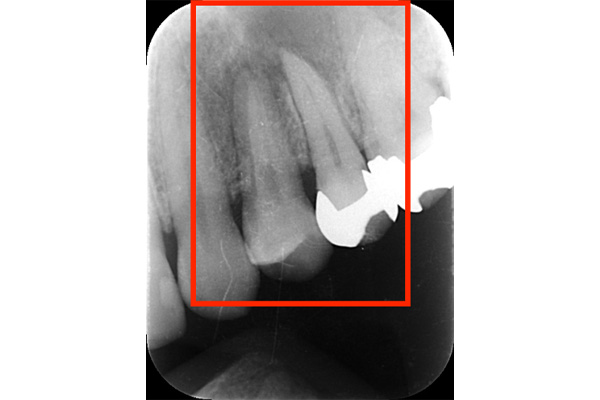

こちらは根の治療の経験がある歯ではありませんが、歯茎が大きく腫れていらした患者様です。レントゲンを撮ってみると原因となっていそうな、2本怪しい歯がありました。過去の虫歯の経緯から後ろの歯の方が怪しいと判断し、1本だけ治療を行いました。

治療後、腫れの大きさの確認のためにCTを撮影すると、上顎洞にまでおよぶ大きな炎症があり、骨が大きくなくなっていることが確認できました。

基礎に忠実に根の中をしっかり清掃し、防腐剤を詰めて経過をみるために3ヶ月後に再度CTを撮影しました。以前とは比べ物にならないくらい、上顎洞の炎症はなくなり。上顎洞を隔てる骨の再生もできました。 またこの治療で一番良かったのは、治療しなければならない歯とそうでない歯を鑑別できたことです。手前の歯はやはり治療する必要がなかったのです。

初診終了後にCT撮影です。上顎洞と歯が連続してしまうくらい炎症が広がっています。

根の先に黒い影があり、2本ともあやしいです。

きっちり清掃を行い防腐剤をつめました。

まだ根の先端に黒い影はあるが、治癒傾向にあると判断できます。